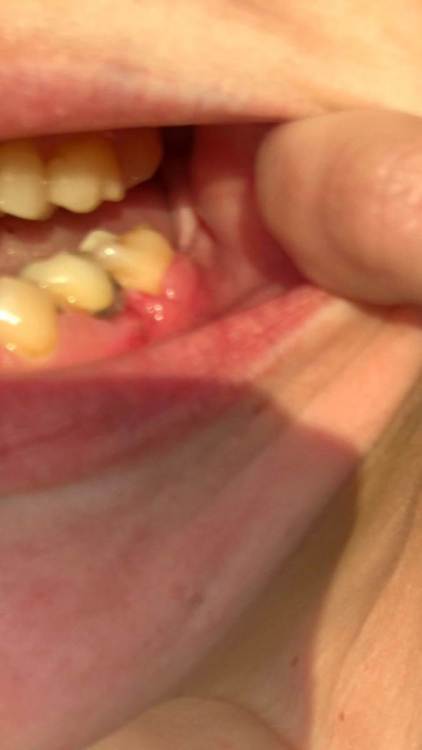

Здравствуйте ! Ситуация следующая - 6 сверху коронка с резекцией , долгое время осталась без антагониста , соотвественно выдвинулась (это уже мое предположение) . Чтобы спасти зуб , доктор принял решение повести гемисекцию корня . После - осталась рассечена десна .. Доктор говорит десна заживет , но визуал мягко говоря напрягает , так как при улыбке у меня это все видно ..

Фото 7,8 - Также была проведена резекция кисты 5 зуба снизу , с коронкой , и установка 7 импланта в качестве антагониста верхней 7 . Одной операцией . Коронка оголилась , швы сняли на 3 день .. доктор также утверждает что в дальнейшем будет все хорошо , зарастет . Также очень смешает внешний вид десны , десна стала волной даже на 6 ..

Прошу прокомментировать и дать рекомендации как возможно исправить внешний вид всех этих манипуляций . И зарастает ли это все ?